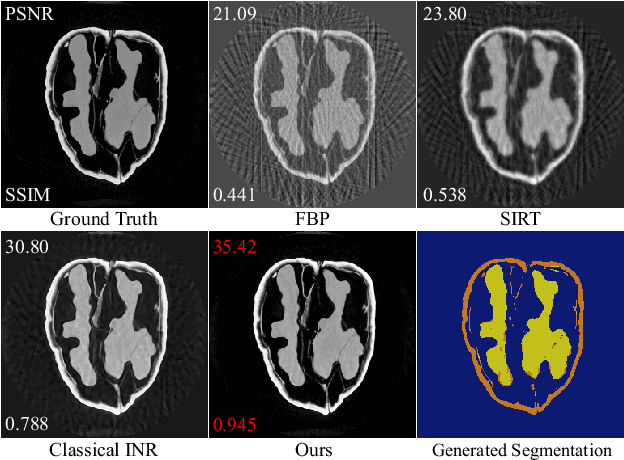

Abstract:Computed tomography (CT) reconstruction plays a crucial role in industrial nondestructive testing and medical diagnosis. Sparse view CT reconstruction aims to reconstruct high-quality CT images while only using a small number of projections, which helps to improve the detection speed of industrial assembly lines and is also meaningful for reducing radiation in medical scenarios. Sparse CT reconstruction methods based on implicit neural representations (INRs) have recently shown promising performance, but still produce artifacts because of the difficulty of obtaining useful prior information. In this work, we incorporate a powerful prior: the total number of material categories of objects. To utilize the prior, we design AC-IND, a self-supervised method based on Attenuation Coefficient Estimation and Implicit Neural Distribution. Specifically, our method first transforms the traditional INR from scalar mapping to probability distribution mapping. Then we design a compact attenuation coefficient estimator initialized with values from a rough reconstruction and fast segmentation. Finally, our algorithm finishes the CT reconstruction by jointly optimizing the estimator and the generated distribution. Through experiments, we find that our method not only outperforms the comparative methods in sparse CT reconstruction but also can automatically generate semantic segmentation maps.